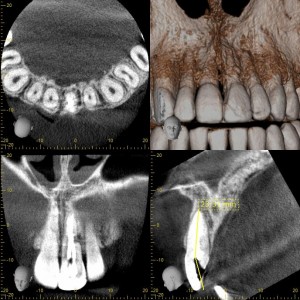

症例です。

コンポジットレジンでの充填を繰り返し、審美障害があり、クラウンでの補綴を希望して来院されました。

外傷の既往がある歯で、歯自体の変色もあります。

デンタルで確認すると歯根のちょうど真ん中辺り、遠心側に歯根吸収を認めます。

精査のため3D撮影を行います。

明らかな破折は認められないものの根管治療では痛みがあり、歯根吸収部位から肉芽組織が入り込んでいる事が想定されました。マイクロスコープで根管を観察すると肉芽様組織が確認出来ました。外傷時のレントゲン等がないので詳細は不明ですが、外傷が原因の歯根吸収だと思われます。根管充填行い症状がないので通常の補綴処置に移行しますが、定期的なレントゲン撮影による経過観察が必要です。